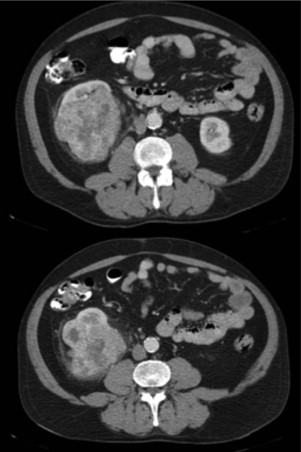

O doente encontrava‐se assintomático, sem hematúria e com bom estado geral. Após discussão multidisciplinar optou‐se por realizar mais 2 ciclos de sunitinib (50 mg/dia 4 semanas com interrupção de 2 semanas) de forma a avaliar a resposta em termos de redução da dimensão do tumor renal primário e do bulking ganglionar justa‐hilar e justa‐Psoas. A nova TAC revelou diminuição da dimensão da massa renal para 9 cm x 7 cm e diminuição do conglomerado adenopático hilar (fig. 3 ).

a) Tumor do polo inferior do rim direito, com 9cmx7 após realização de sunitinib ...

Figura 3.

a) Tumor do polo inferior do rim direito, com 9 cm x 7 após realização de sunitinib (2 ciclos), b) conglomerado adenopático hilar e justa, Psoas.